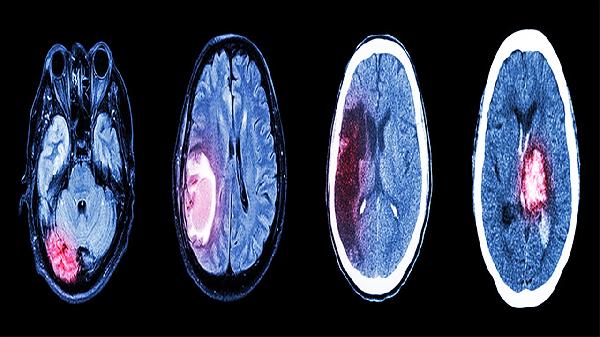

药物中的活性成分可促进脑细胞代谢,改善认知功能。对于脑卒中后的功能恢复,以及轻度认知障碍患者有一定帮助。使用期间应配合康复训练和适量脑力活动。

五、辅助治疗脑血管疾病

作为辅助用药,久强脑立清常用于治疗脑动脉硬化、脑供血不足等慢性脑血管疾病。它能够延缓脑血管病变进展,但须配合基础疾病治疗,不能替代降压、降脂等主要治疗药物。